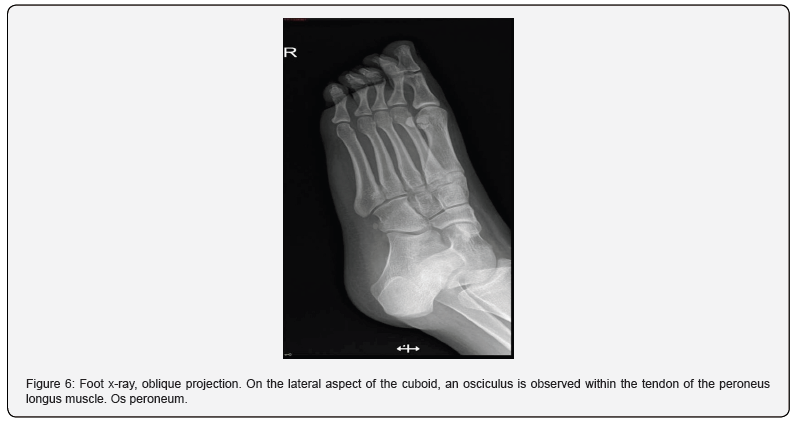

Finally, the accessories of the fifth metatarsal that are close to the styloid process and include the Os Vesalianum with a frequency of 15%, given by the fusion defect of the secondary ossification nucleus and is located in the peroneus brevis tendon; followed by Os peroneum, more common, at 26%, is an ossicle on the lateral aspect of the cuboid within the tendon of the peroneus longus muscle (Figure 6) [4,10].